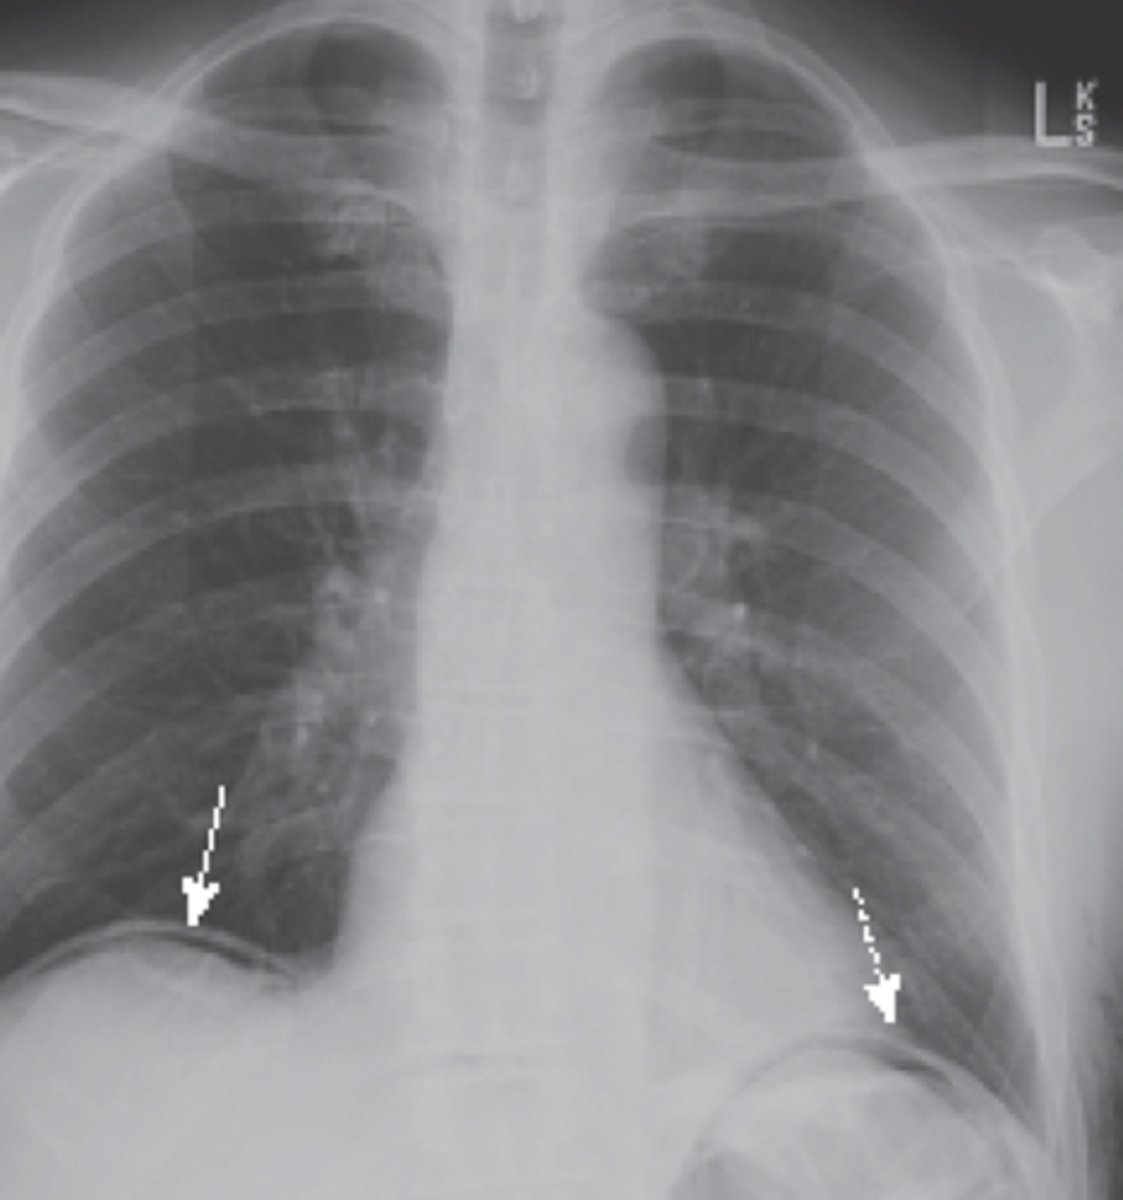

is perforation of a hollow viscus structure a medical emergency

yes

extraluminal air will rise to the highest part of the abdomen which is under the

diaphragm

crescentic lucency (extraluminal air)

types of extraluminal air

pneumoperitoneum, retroperitoneal free air, air in bowel wall, air in biliary system

pneumoperitoneum

retroperitoneal free air

air in bowel wall

air in biliary system